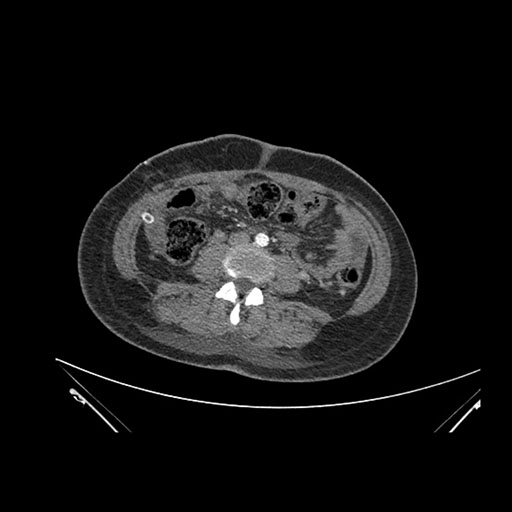

Look through the patient's CT scan to identify any areas of concern for the necessary procedure.

Coronal Venous